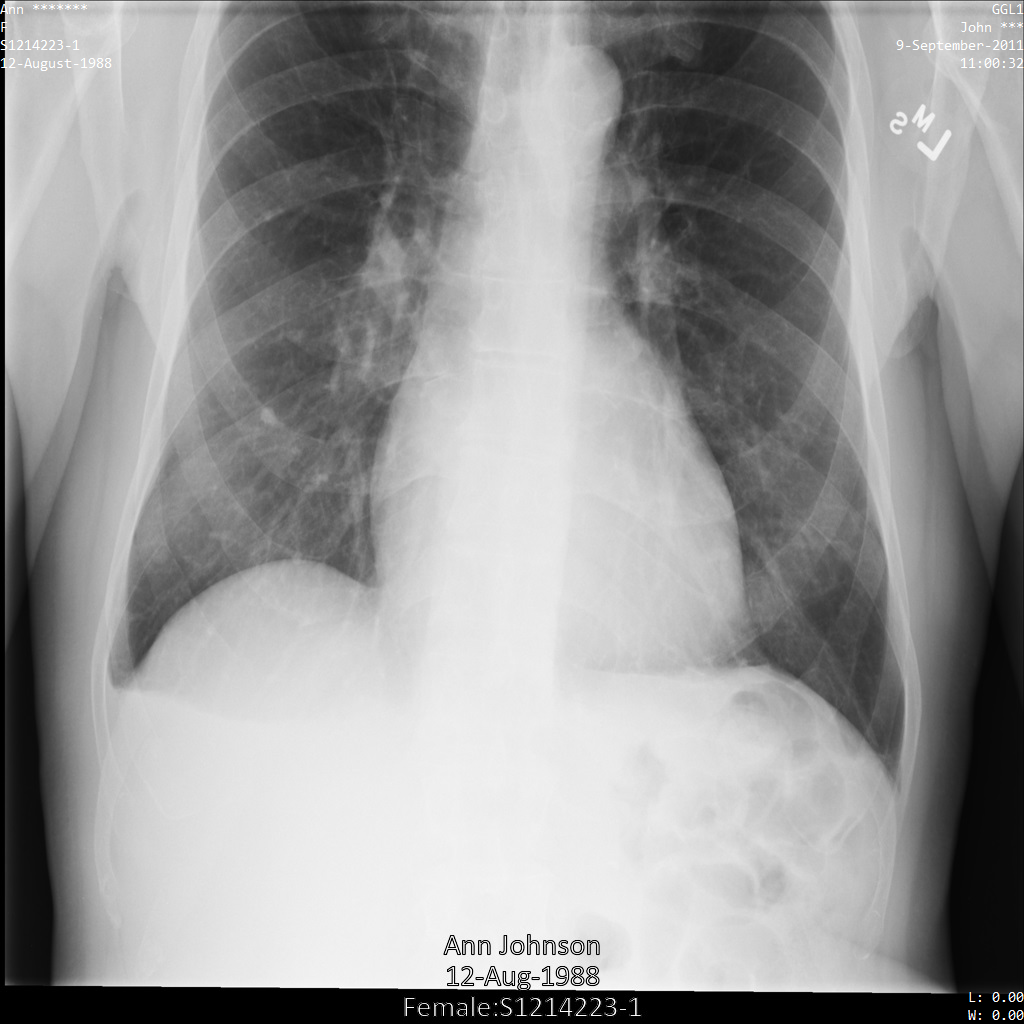

Después de enviar la imagen a la API de Cloud Healthcare mediante las opciones REDACT_ALL_TEXT y DEIDENTIFY_TAG_CONTENTS, la imagen aparece de la siguiente manera. Observa los siguientes cambios:

- Los nombres en la esquina superior izquierda y en la esquina superior derecha de la imagen se transformaron con una

CryptoHashConfig - Las fechas en la esquina superior izquierda y derecha de la imagen se transformaron con un

DateShiftConfig - Se oculta el texto grabado que aparece en la parte inferior de la imagen.